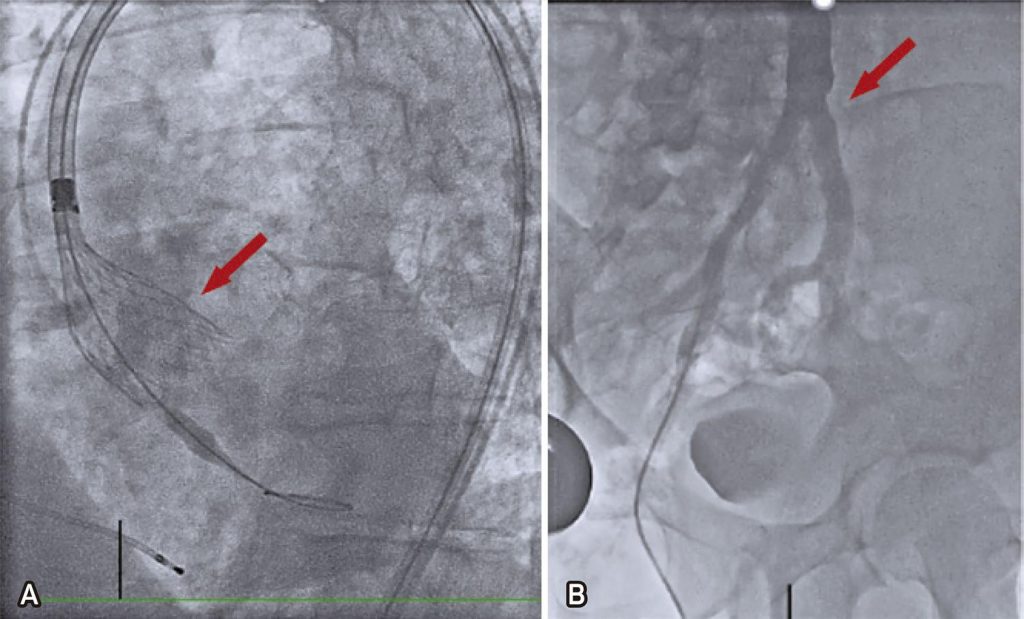

Figura 3

Angiografia. (A) Liberação (seta) de prótese autoexpansível CoreValve Evolut R 34mm (Medtronic®, Santa Rosa, CA). (B) Resultado da bifurcação da artéria ilíaca comum após tratamento com litotripsia intravascular (seta).